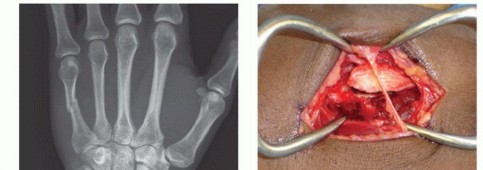

TECH FIG 4 • A-C. Patient with torsional injury to long and ring fingers leading to spiral fractures of the third and fourth metacarpals. The combined injury made it possible for malrotation to develop. D.

TECH FIG 4 • (continued) G,H. Motion at 6 weeks after surgery. The periosteum is elevated at the fracture site to assist with assessment of fracture reduction. As much of the interosseous muscle is left attached to the metacarpal as feasible to preserve blood supply to the bone.The fracture is reduced and provisionally stabilized with reduction clamps (TECH FIG 4D).

LAG SCREW FIXATION

Long oblique and spiral fractures whose lengths are at least twice the diameter of the bone at the level of the fracture are amenable to limited fixation with screws only (see TECH FIG 4A-C).Appropriately sized lag screws (1.4 to 2.7 mm) are placed. Typically, two or three screws are used (TECH FIG 4E,F).The first screw is placed perpendicular to the fracture in order to compress it and the second screw is placed perpendicular to the bone to resist longitudinal forces.In order to get proper compression with a lag screw construct, it is important to overdrill the near cortex.When using a 2.0-mm screw system, a 1.5-mm drill bit is used to drill both cortices. The near cortex is then overdrilled with a 2-mm drill bit.A countersink is used to maximize contact between the head of the screw and the bone. The size of the screw is measured and an appropriately sized screw is placed.The periosteum and interosseous muscle fascia are reapproximated to cover the screws. The juncturae tendinum are repaired and the skin is closed in standard fashion.The hand is then immobilized with the MP joints flexed 70 to 90 degrees with a forearm-based splint. Early motion can be started as early as 4 to 7 days, depending on fracture stability (TECH FIG 4G,H).